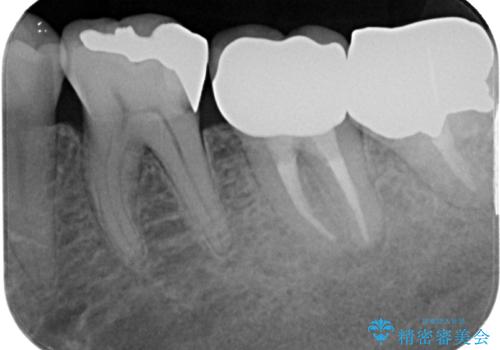

根管治療後6か月が経過してレントゲンを撮影したところ、非常に大きかった病変が小さくなっていることが確認されました。

今後も経過観察を継続していくこととなります。